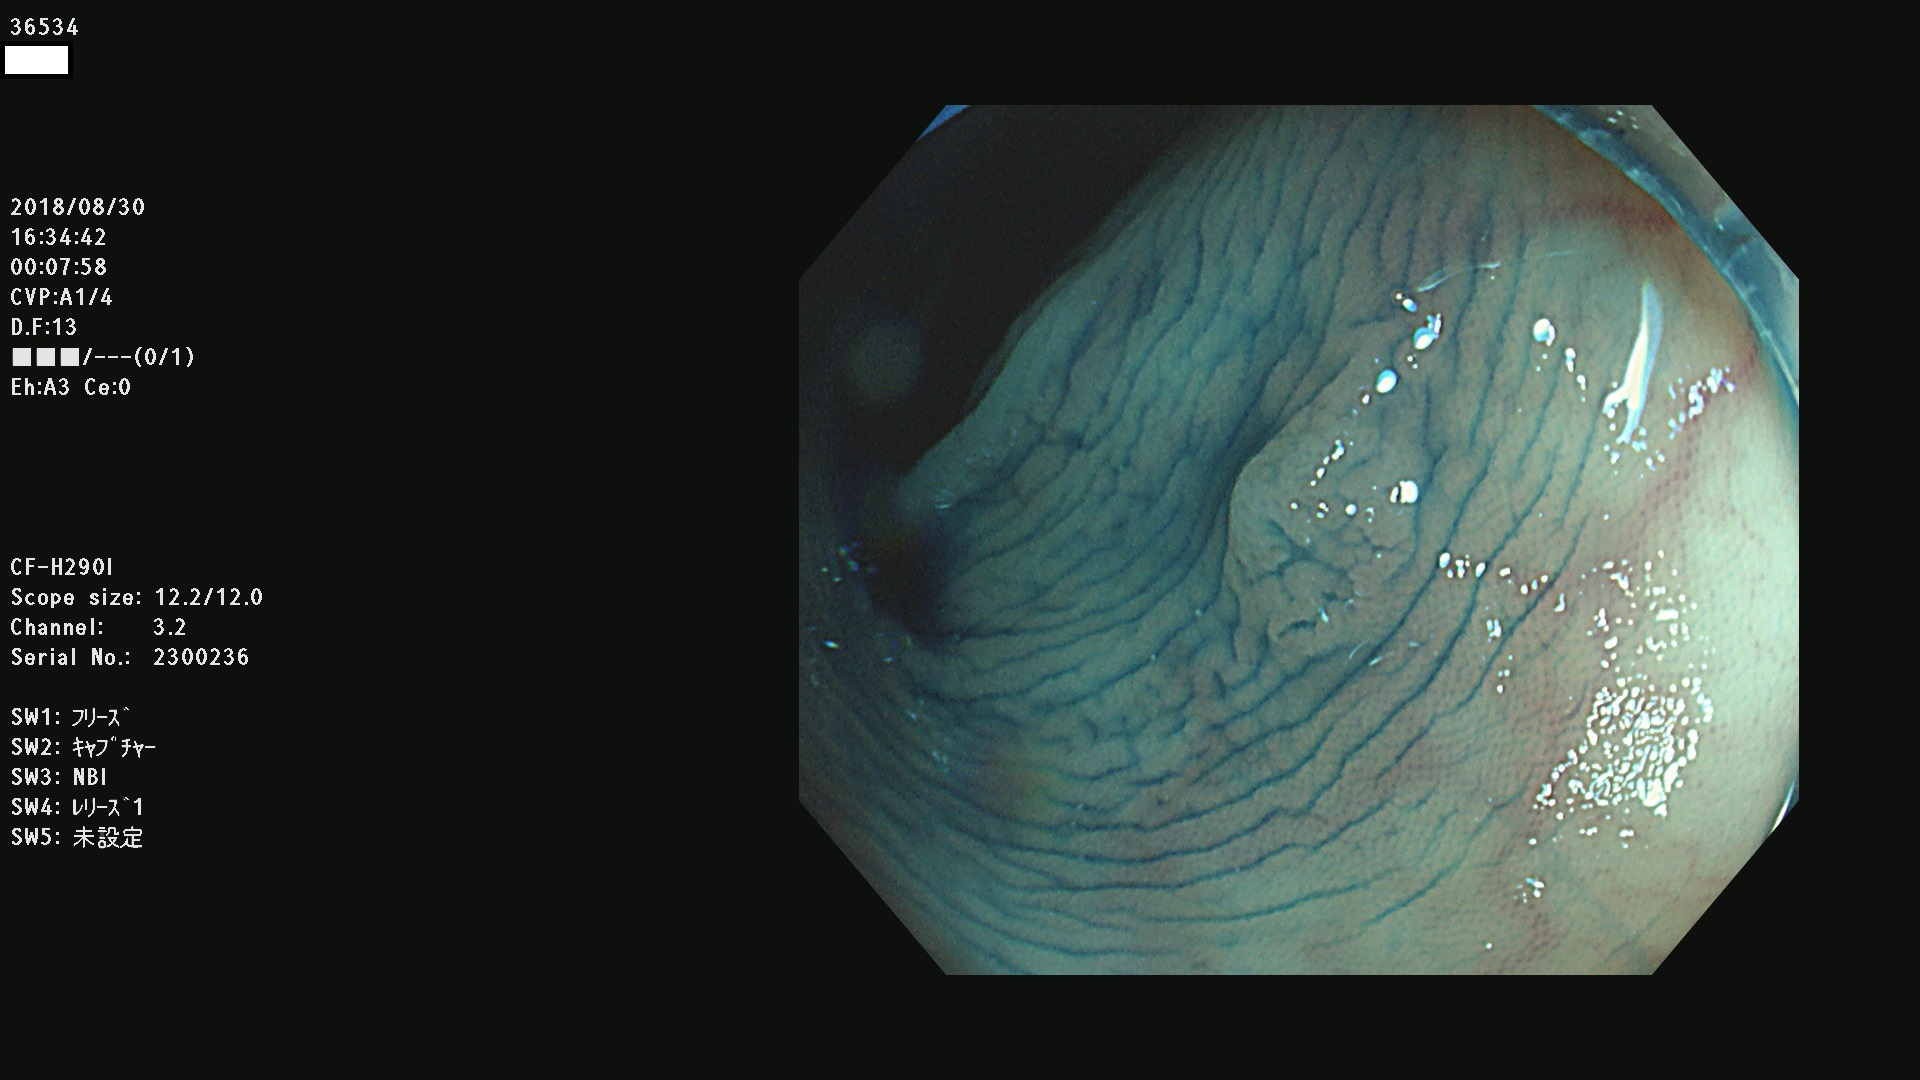

発見困難で危険性の高い平坦型病変(上記100名より抽出)

虫垂SSAP